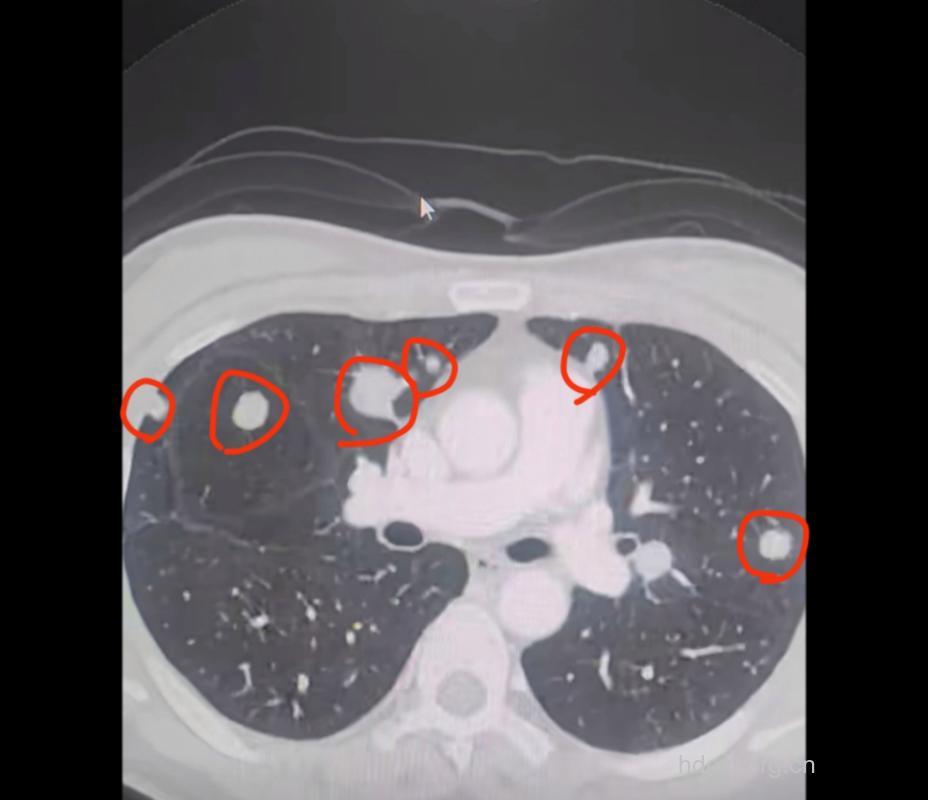

肺转移瘤由身体其他部位的恶性肿瘤转移而来,可以是血行播散、淋巴道转移或邻近器官直接侵犯。多见于绒毛膜癌、乳腺癌;还见于恶性软组织肿瘤、肝癌、骨肉瘤和胰腺癌;也见于甲状腺癌、肾癌、前列腺癌和肾胚胎癌等。

血行转移最为常见,是肿瘤细胞经腔静脉回流到右心而转移到肺。瘤栓到达肺小动脉及毛细血管后,浸润并穿过血管壁,在周围间质及肺泡内生长,形成肺转移瘤。淋巴道转移由血行转移至肺小动脉及毛细血管床,穿过血管壁侵入支气管血管周围淋巴结,癌瘤在淋巴管内增殖,形成多发的小结节病灶,通过淋巴管在肺内播散。肿瘤向肺内直接转移的原发病变为胸膜、胸壁及纵隔的恶性肿瘤。